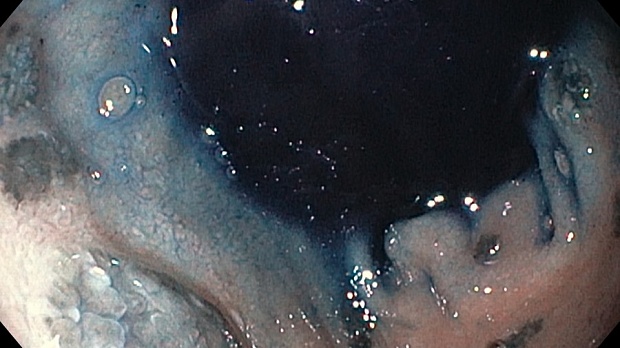

меланома ДПК.jpeg)

меланома ДПК.jpeg)

меланома ДПК.jpeg)

меланома ДПК.jpeg)

Эзофагогастродуоденоскопия диагностическая

12-кишка: Просвет луковицы двенадцатиперстной кишки обычный, содержит небольшое количество желчи, перистальтика активная , слизистая оболочка розового цвета, ворсинки сохранены. Так же прослеживаются пигментированные образования от 2мм до 8мм. серо-синюшного оттенка. Постбульбарном отделе множественные пигментые образования до 10мм, единичные кратообразные пигментные образования до 15мм, глубиной до 5мм., дно покрыто серым фибрином. Биопсия 2-а кусочка.

Заключение: ГПОД. Грыжевая гастропатия. Эрозивная гастропатия антрального отдела желудка. MTS Меланома ЛДПК, залуковичного отдела. Биопсия.